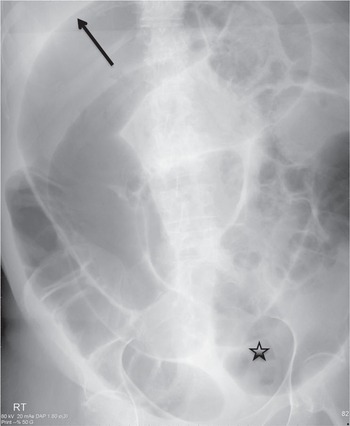

一番の贈り物 Dynamic Radiology of the Abdomen: Normal and Pathologic 洋書

一番の贈り物 Dynamic Radiology of the Abdomen: Normal and Pathologic 洋書

Dynamic Radiology of the Abdomen: Normal and Pathologic,

Dynamic Radiology of the Abdomen: Normal and Pathologic, Dynamic Radiology of the Abdomen: Normal and Pathologic,

Dynamic Radiology of the Abdomen: Normal and Pathologic, Meyers' Dynamic Radiology of the Abdomen: Normal and,

Meyers' Dynamic Radiology of the Abdomen: Normal and, Radiologia Dinâmica do Abdome | Amazon.com.br,

Radiologia Dinâmica do Abdome | Amazon.com.br, Imaging of the Abdomen (2.10) - Intensive Care Medicine

Imaging of the Abdomen (2.10) - Intensive Care Medicine洋書 [A12298828]IB Chemistry Course Book: Oxford IB Diploma Programme 2014 Edi